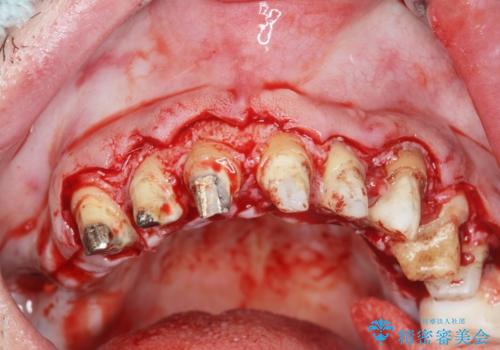

歯周組織検査を行うと歯ぐきからは容易に出血し、X線検査より歯とセラミッククラウンの適合が悪い(ピッタリと合っていない)状態が示唆され、歯ぐきの炎症を惹起している状態でした。

セラミッククラウンを除去し仮歯を装着し、歯周外科手術を行い歯ぐきの状態を改善したのち、適合の良いセラミッククラウンを再作製をする治療計画としました。

見た目の良いクラウンが装着されていても、歯ぐきの状態が悪ければ違和感や歯ぐきの腫れ、臭いの元となっていることが多く見られます。